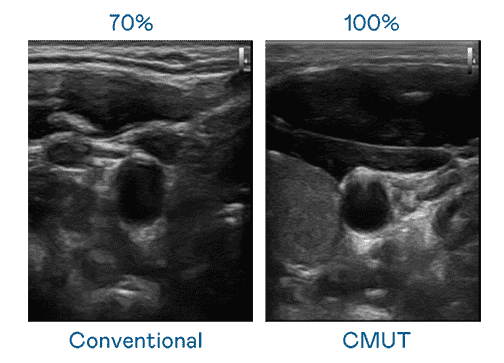

CMUT 技术是一种用电容式微机电元件来产生超音波讯号的技术。。。与传统 PZT 压电式技术相比,,,CMUT 频宽增加 30%,,,,更宽频的超音波讯号让影像解析度大幅提升,,,是实现高影像品质医疗超音波扫描、、、促进精准医疗发展的关键技术。。。

超音波影像的解析度高低,,,首先取决于探头能发出的讯号频宽。。z6mg·人生就是博 CMUT 可提供高清晰的超音波讯号,,,,提供高频宽、、、、高灵敏度、、、、影像纹理细节更高的超音波影像,,,,协助医护人员缩短影像判读时间及利用精准的医疗影像进行诊断。。。。